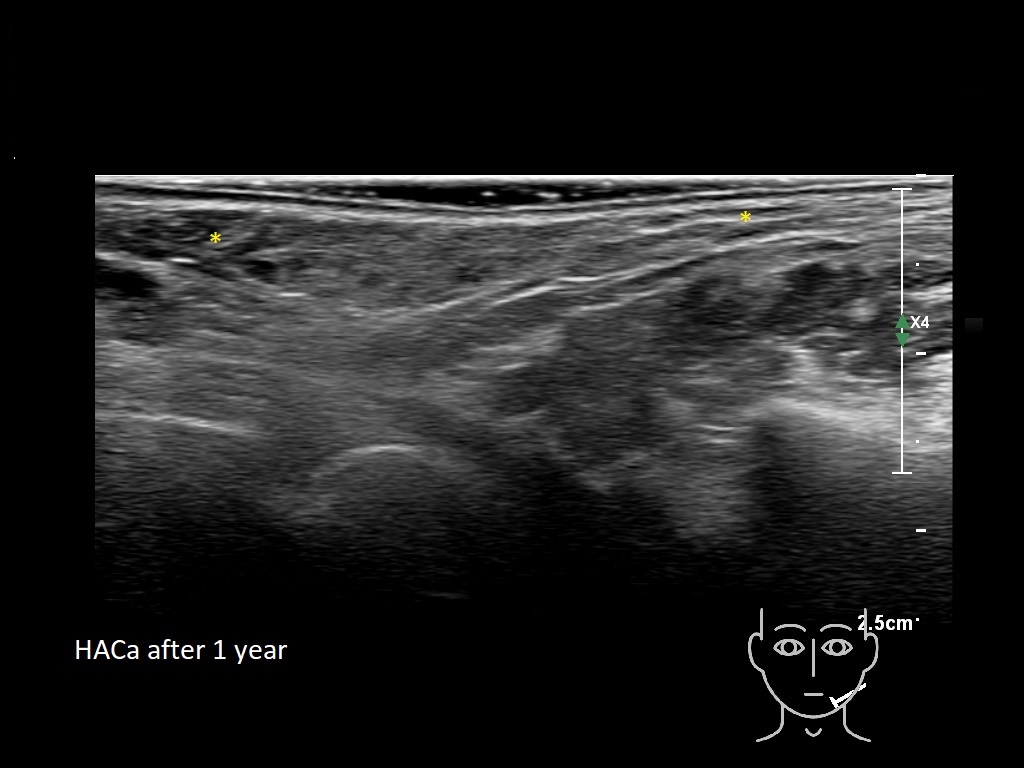

Draw in the image on the right where the fillers are located. To check if your answer is correct, please click on the secondary image.

Fillers

HAca 1b e

HACa 4b e

HACa 5b e